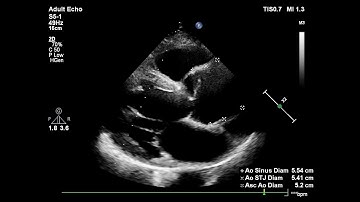

Measuring the Ascending Aorta Using Echocardiography